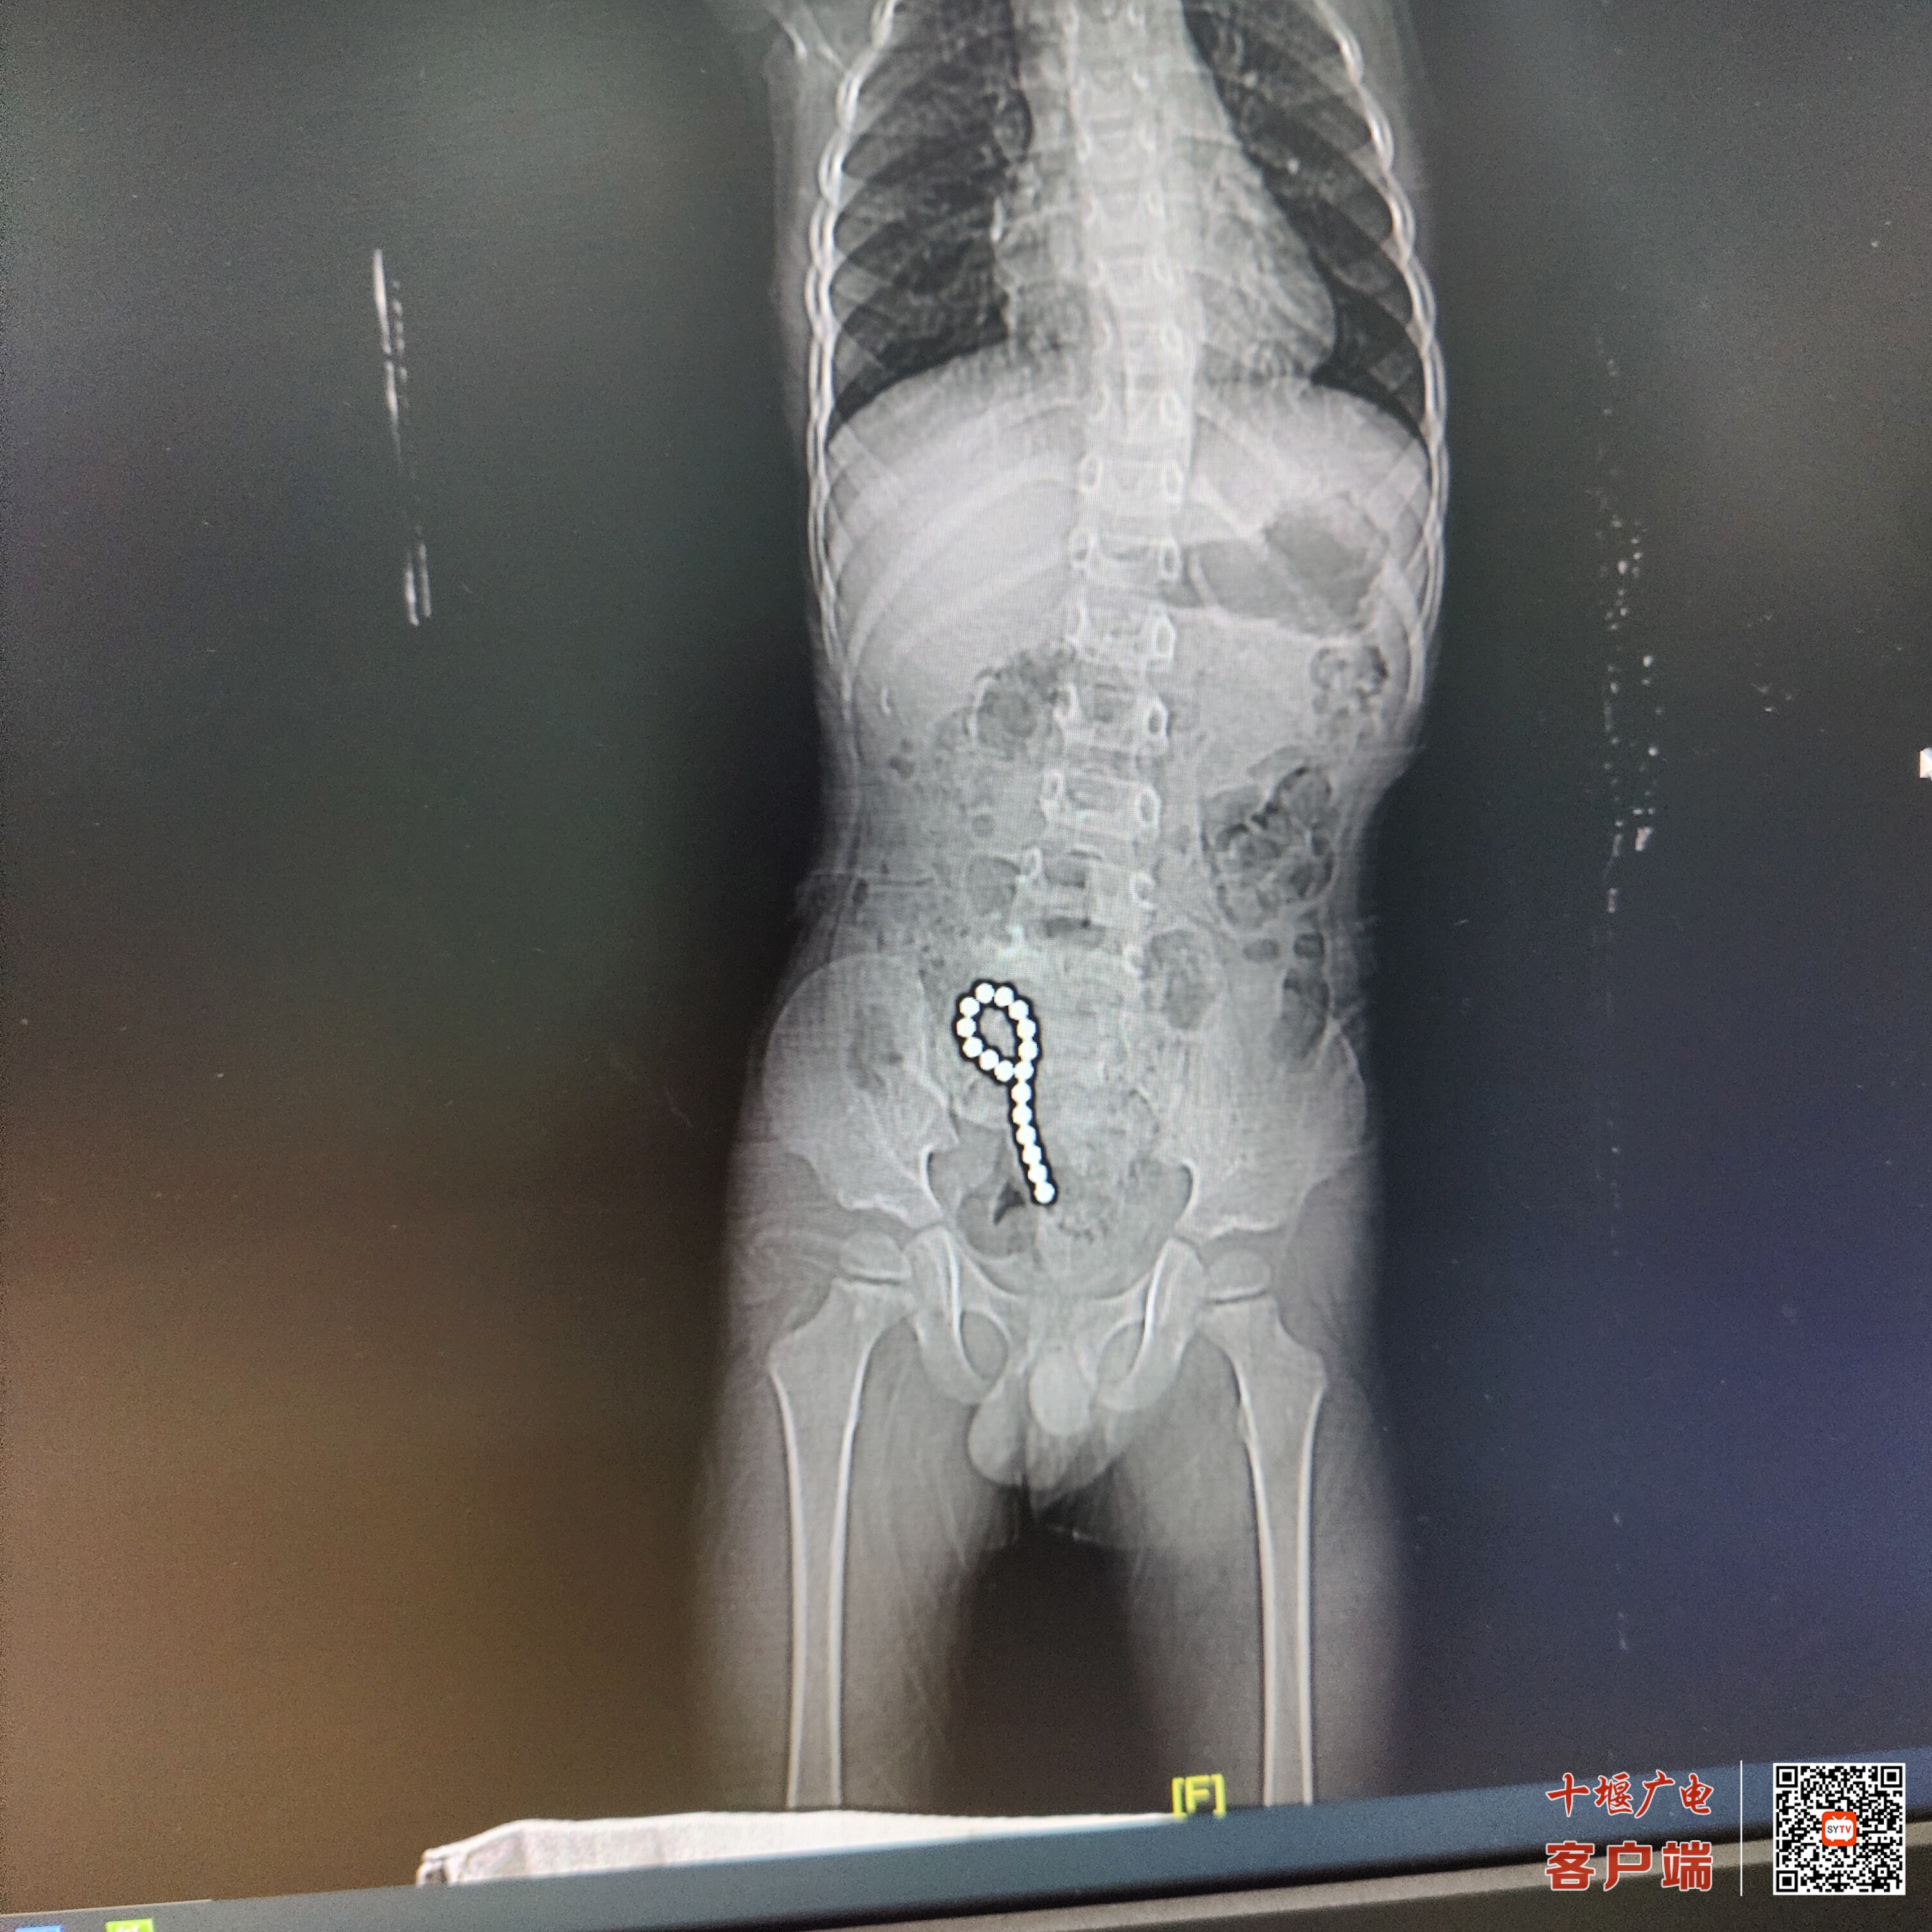

十堰市太和医院小儿外科主任屈振繁告诉记者,在医院拍片时,我们就发现腹腔里面有一个环行异物,当时家长就很紧张,考虑到是什么东西吞进去了。因为小患者的家属自己也不清楚他到底吃进去的是什么,但从外形上看,医生判断是磁力珠。

十堰市太和医院小儿外科副主任赵名君告诉记者,为了验证是不是磁力珠,我们就用磁铁试着吸了一下肚皮,结果发现肚皮就随着磁力珠的活动给吸起来了,这样就更加确定它就是误食了磁力珠造成的肠梗阻。

由于磁力珠相互吸引,把小肠壁压住,导致小肠壁缺血坏死,直到穿成五个孔,最后连成一串。医生立即在腹腔镜辅助下,从肚脐部开个小口到小肠内取出17颗磁力珠,随后医生做了肠粘连松解和肠穿孔修补术,一个多小时手术很顺利。